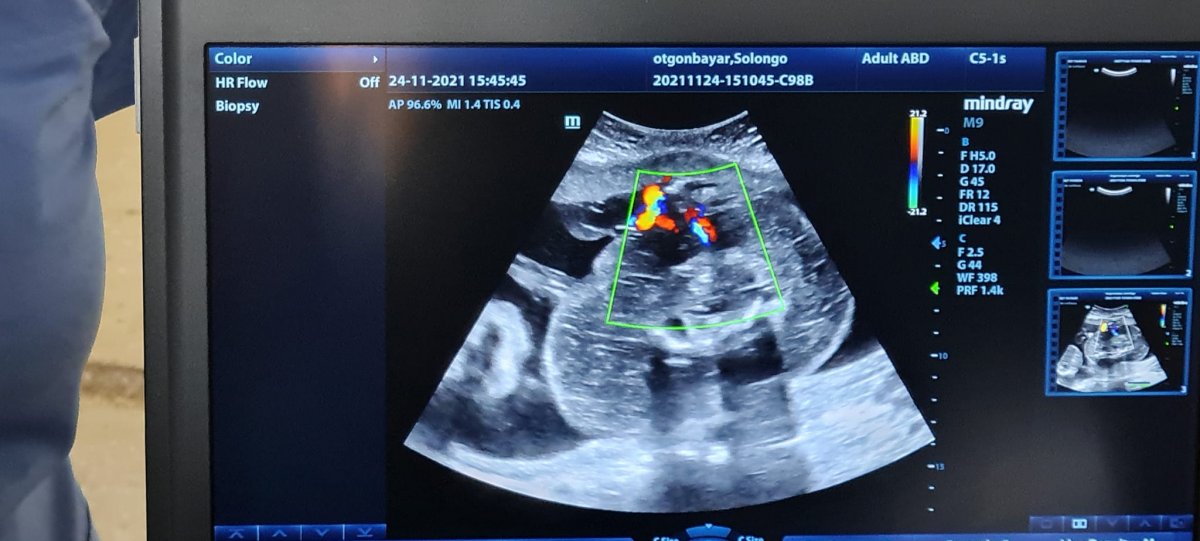

Улсын хоёрдугаар төв эмнэлэг, Эх хүүхдийн эрүүл мэндийн үндэсний төв эмч нар хамтран 27 дахь 7 хоногтой үеийн урсгалыг умай дотор нь аблацийн аргаар солих мэс ажилбарыг (Twin Reversed Arterial Perfusion) өнгөрсөн оны 11 дүгээр сарын 24-ний өдөр анх удаагаа амжилттай хийсэн билээ.